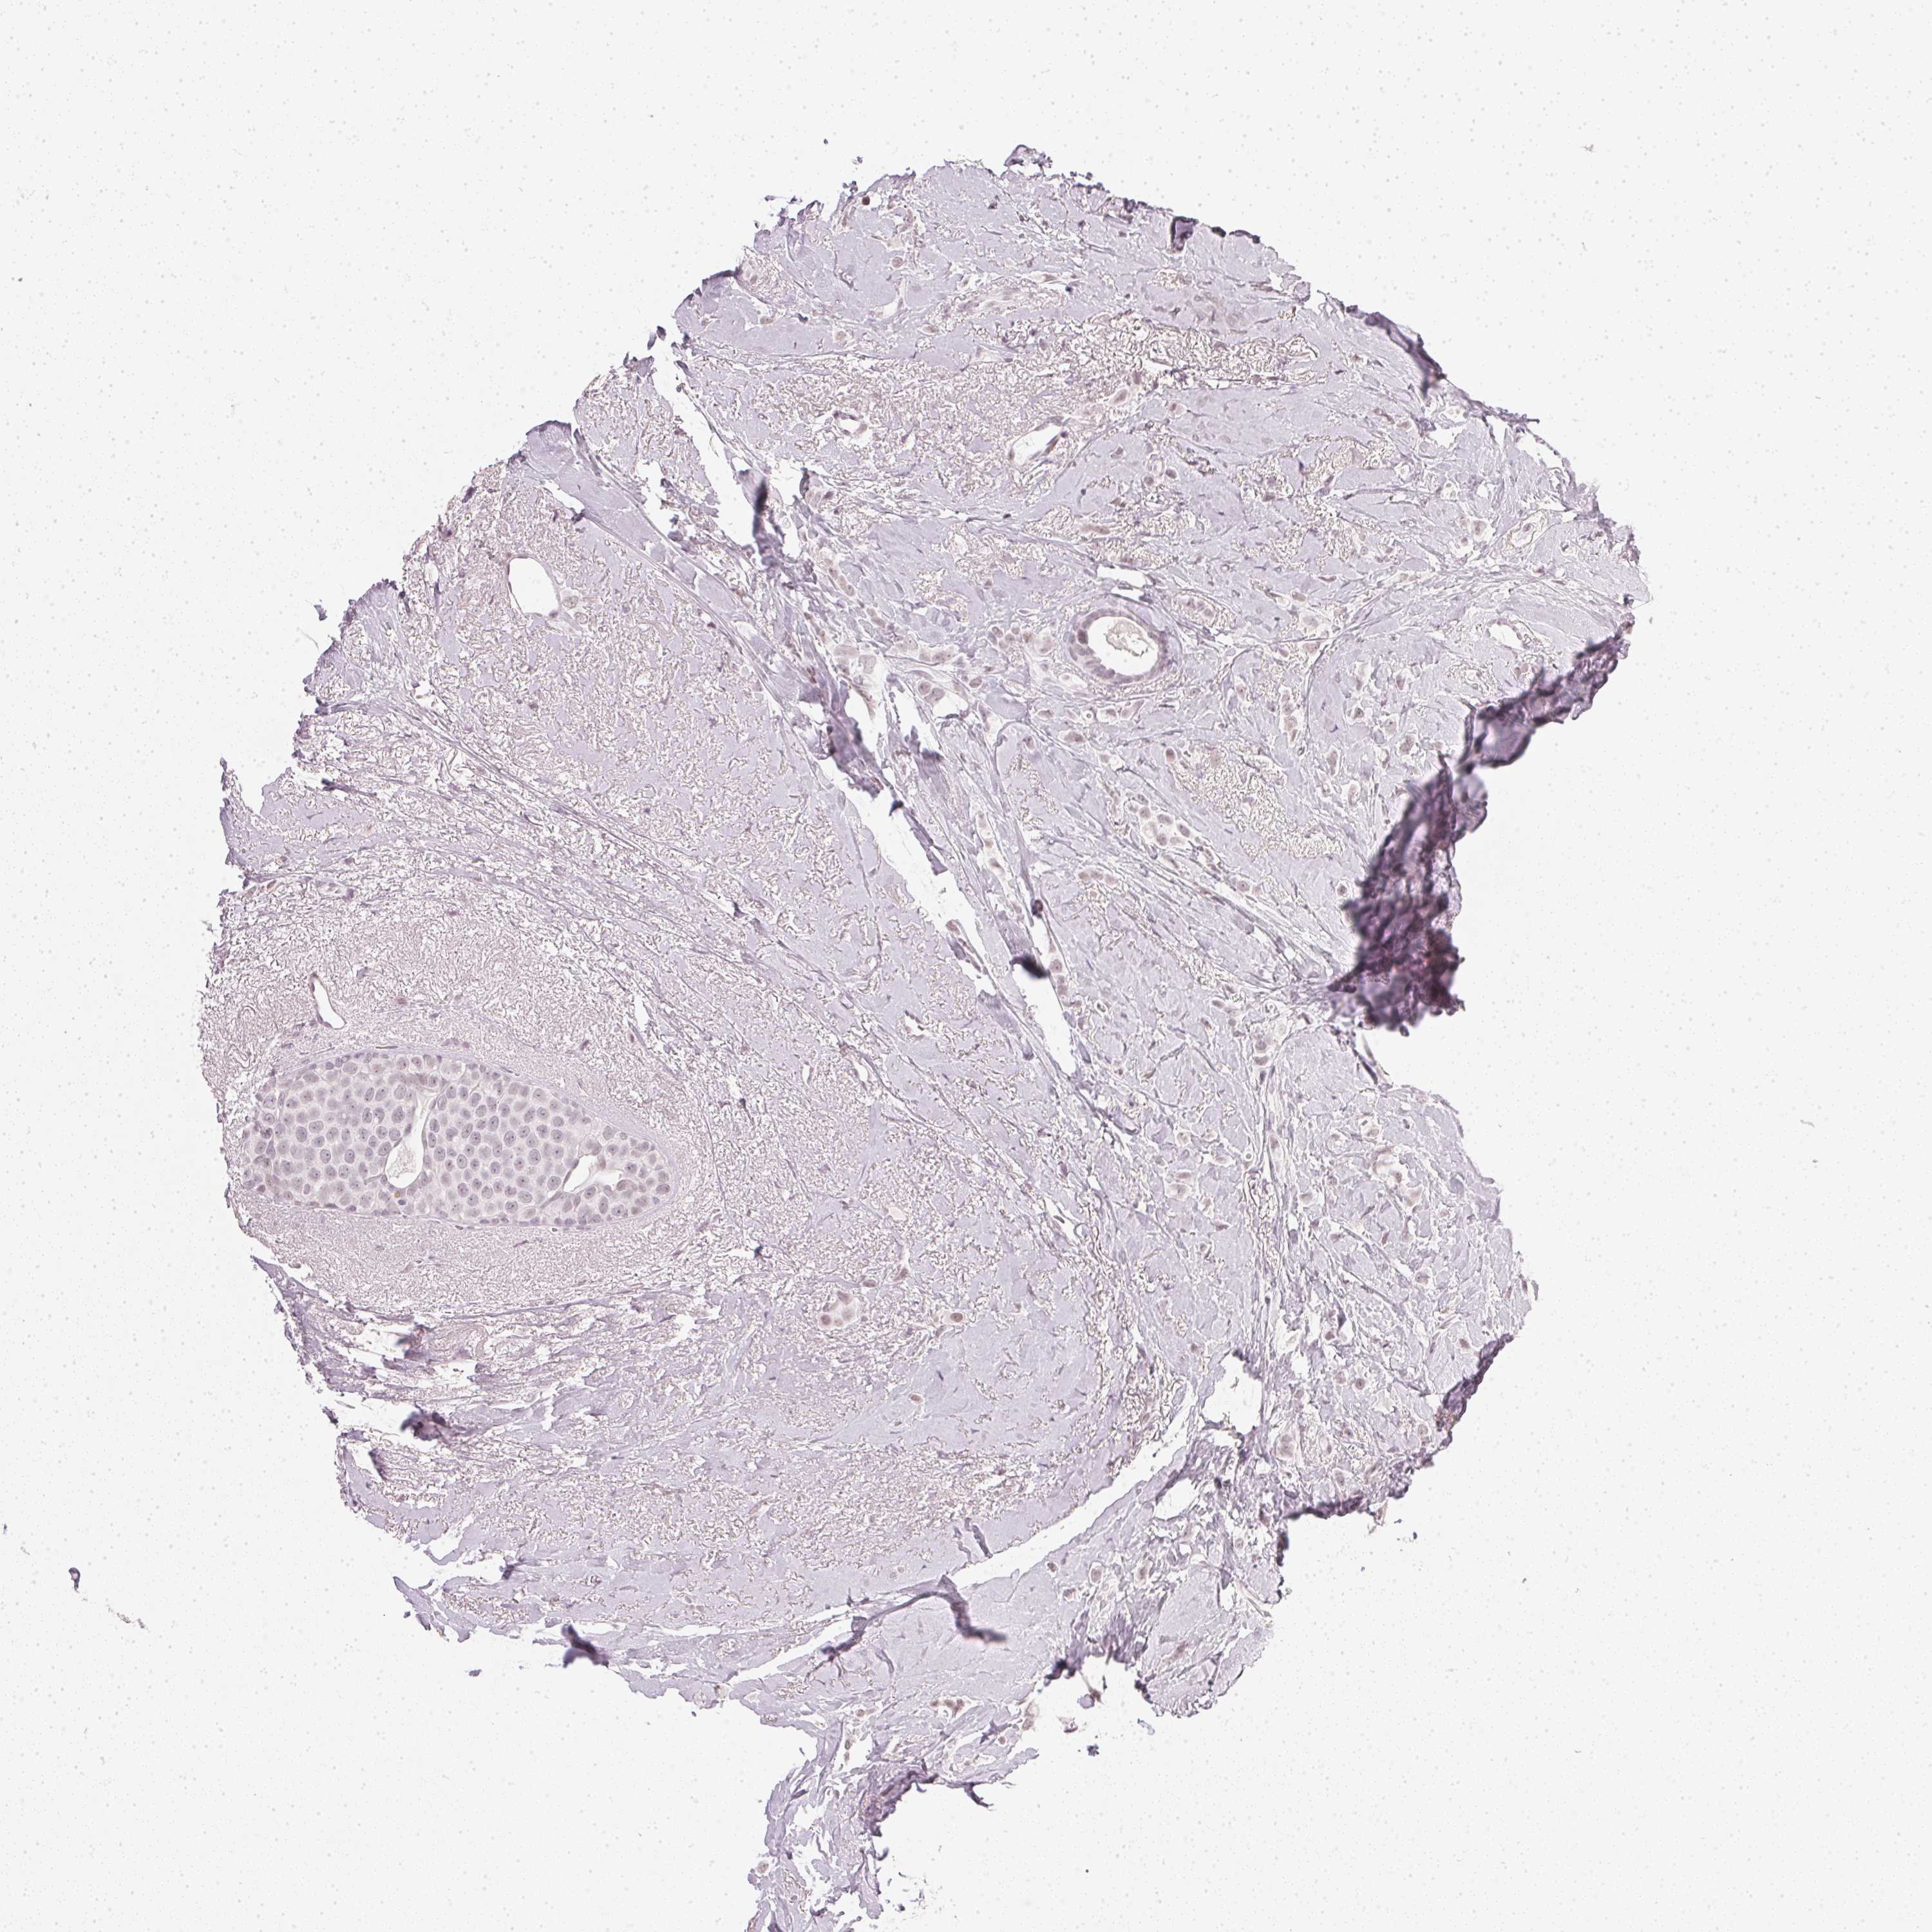

BRCA TCGA BRCA VALIDATION PROTEIN EXPRESSION

Breast cancer

Human cancer